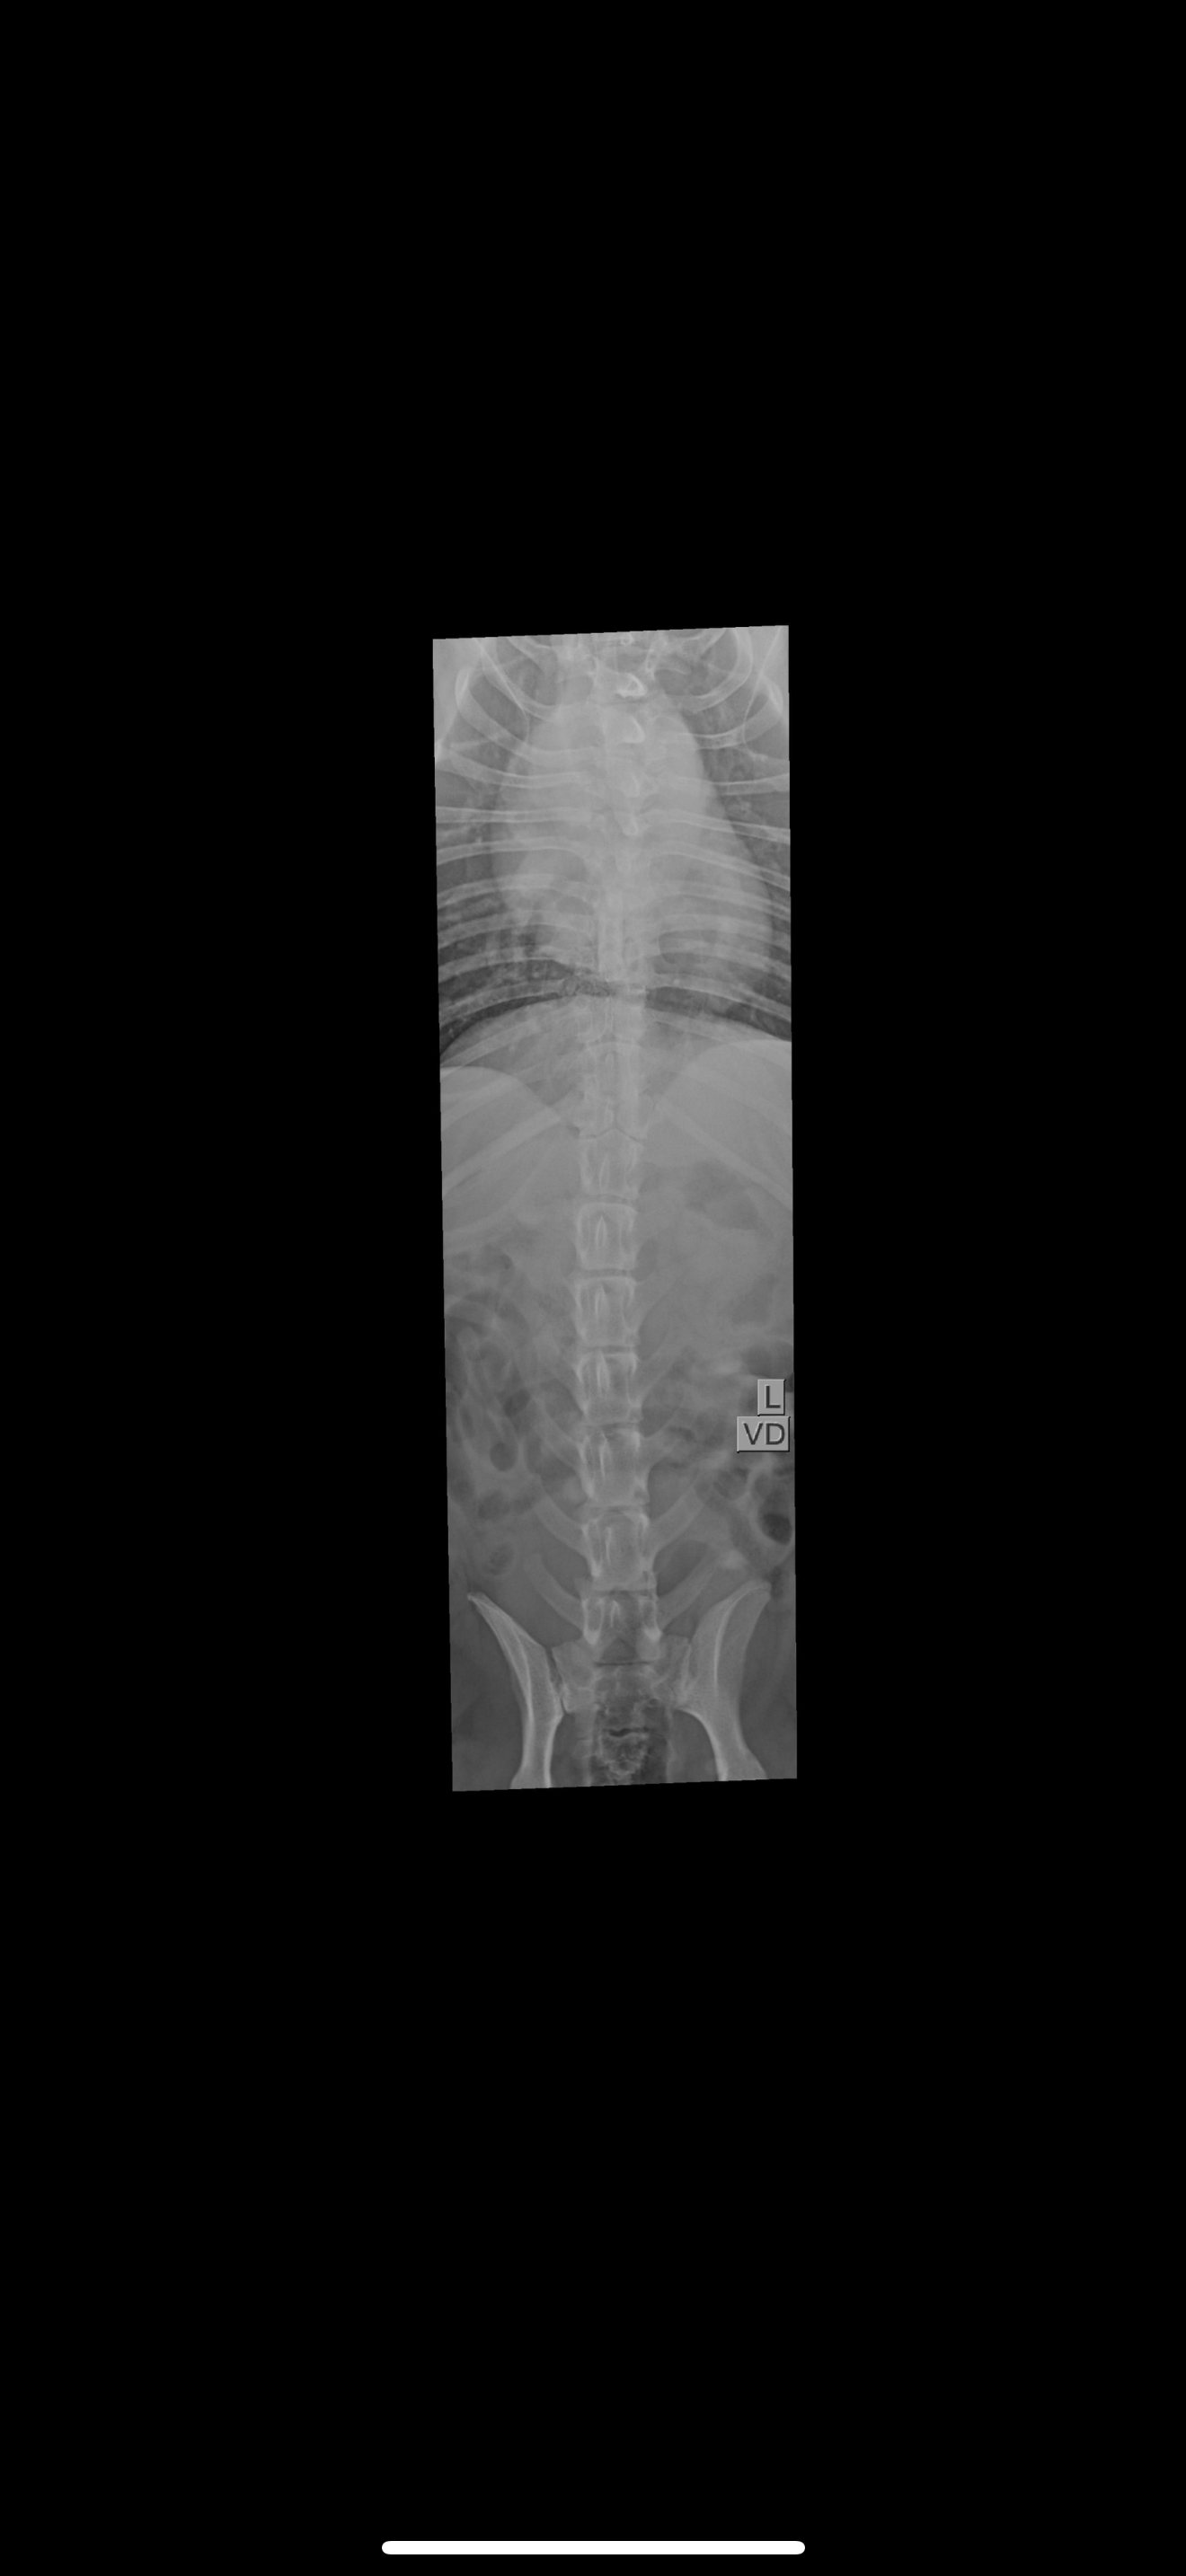

We’re reaching out with heavy hearts to ask for your support for our Moxie girl.A few days ago, she was diagnosed with IVDD (Intervertebral Disc Disease), and our world has been turned upside down. It’s left her paralyzed, and seeing her struggle has been absolutely heartbreaking. If you know Moxie, you know she’s the happiest, silliest, most loving little dog always asking to be held or played with.She’s always been the life of the party ! wiggling, dancing, and greeting everyone who walks through the door like they’re her favorite person in the world.We’ve been told that an MRI and surgery are her best chances to regain mobility and live the happy, full life she deserves. Unfortunately, the cost of these procedures is more than we can manage on our own. We’re doing everything we can, but we need a little help to give her this chance.